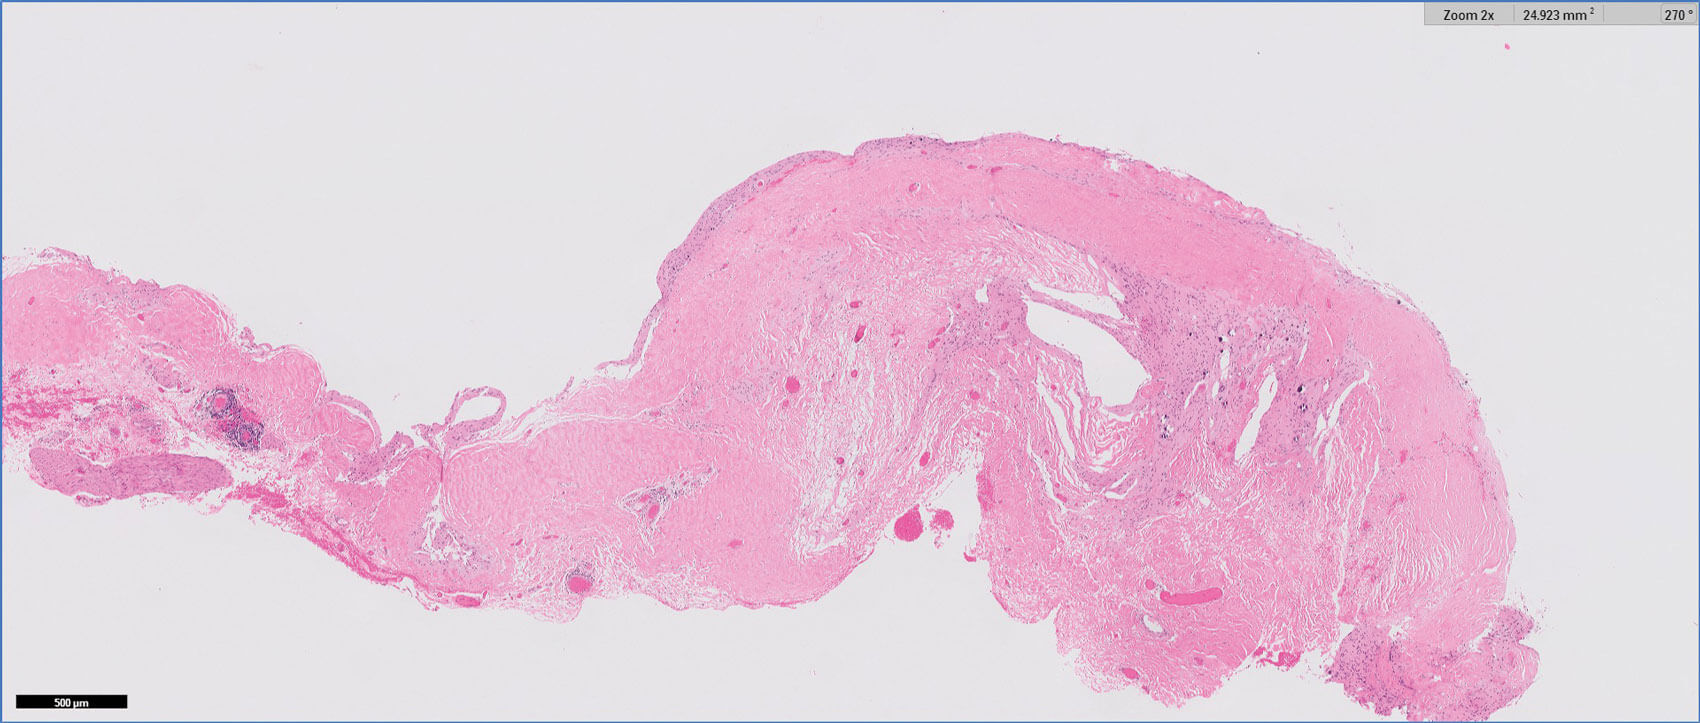

Figure 1: H&E 2x.

Figures 1-3 show representative H+E-stained sections and glial fibrillary acidic protein (GFAP) immunohistochemistry of the lesion.

- Figures 1 and 2 show a thick collagenous cyst wall lined by glial cells. Immunohistochemical staining is strongly positive for GFAP (Figure 3). Synaptophysin did highlight the neuroretinal tissue (not shown here). Pancytokeratin (AE1/AE3) was negative.

- The overall features are those of a colobomatous cyst associated with the known clinical history of microphthalmia.

The cyst lining is of disorganised primitive neuroretinal glial tissue, and can show retinal architecture, photoreceptor differentiation or rosette formation. The cyst wall lacks choroidal tissue.